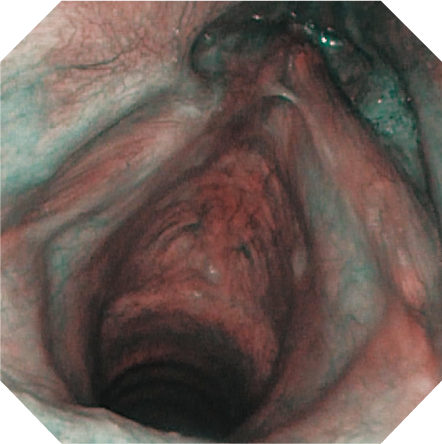

ENF-V3 の先端外径は、2.6mm。さらに、先端外径と挿入部外径との差をわずか0.3mm に縮小。小児や鼻腔の狭い患者さんへの挿入も容易となり、より苦痛の少ない診断をサポートします。

また、CCD の高密度化により、画質の向上を同時に実現しました。NBI 観察も可能です。

通常光

NBI

NBI(Narrow Band Imaging)は、粘膜表面上の血管と組織をより見えやすくする、オリンパス独自の光学的な画像強調技術です。2 つの特定の帯域に狭められた光が、ヘモグロビンによって強く吸収されます。モニター上では粘膜表層上の毛細血管が茶色に、粘膜下組織内部の血管が青緑色に表示されます。